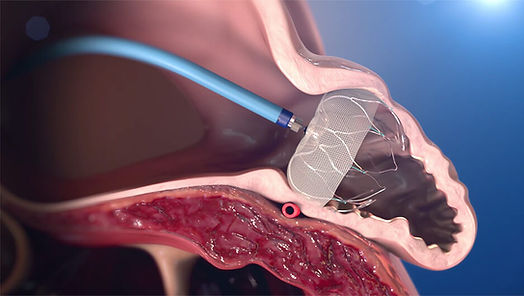

Watchman, kalbin atriyal yüzünü kaplayan bir kumaştan ve kendinden genleşebilen sabitleme pervaneli nitinol çerçeve yapısından oluşur. Nitinol çerçevede yer alan küçük kancalar, cihazın SAA duvarına tutunmasını sağlar. Watchman’in SAA ostiyum çapından daha büyük olması gerekir, bu yüzden farklı vakalar için cihazın 21-33 mm arasında beş farklı boyutu geliştirilmiştir (2).

Cihazın implant prosedürü genellikle bir saat sürer ve hasta o günü hastanede geçirir. Hastaya genel anestezi altında transseptal tekniği kullanılarak kateterizasyon uygulaması gerçekleştirilir ve hangi boyutta Watchman cihazının yerleştirileceğini belirlemek için hastanın sol atriyal uzantısı ölçülür. Bunun için ise ekokardiyografi ve bu yöntemin yetersiz kaldığı durumlarda transözofageal ekokardiyogram (TEE) kullanılır. Bu gerekliliğe yol açan durumlar; kalpte pıhtı veya enfeksiyon varlığının araştırılması, yapay kapak işlevlerinin değerlendirilmesi, kalp kapak tamiri veya kalp kapaklarının kapatılması ameliyatları sırasında ve sonrasında ameliyatın başarı durumunu ölçmektir.Doğru boyutlarda cihaz seçildikten sonra Watchman kılıfı, femoral venden girilerek tel üzerinden sol atriyuma ilerletilir. Erişim kılıfı pigtail kateter üzerinden SAA’nın distal kısmına gönderilir. Dağıtım sistemi hazırlanıp erişim kılıfına yerleştirildikten sonra Watchman de SAA’ya yerleştirilir. Cihaz uygulamaya geçmeden önce son kez floroskopi ve TEE ile kontrol edilir. Son olarak cihaz açılır, böylece SAA kapanır ve hastalar operasyon sonunda antikoagülan almayı durdurup inme riskini azaltmış olurlar (1).